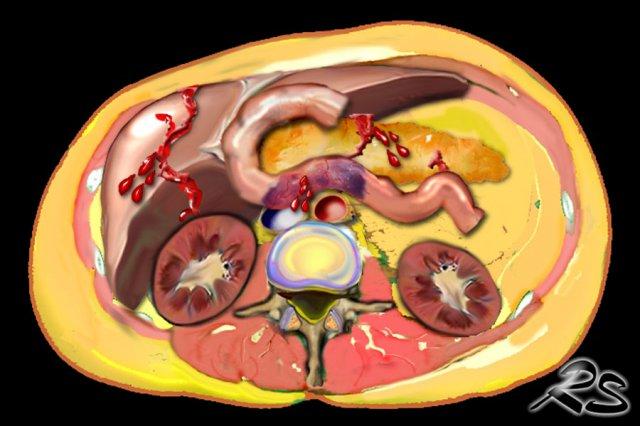

Chấn thương bụng

Nhìn chung, chấn thương tạng ở trẻ em là hiếm gặp, tuy nhiên khi được chẩn đoán, các chấn thương bụng thường gặp ở trẻ bị bạo hành bao gồm:

- Rách gan

- Tụ máu tá tràng

- Rách tụy

Chấn thương tạng được ghi nhận qua khám nghiệm tử thi ở trẻ nhũ nhi, nhưng hiếm khi được ghi lại trên hình ảnh học ở các nạn nhân còn sống dưới 1 tuổi.

Ước tính có khoảng 2-10% tổng số chấn thương bụng là do bạo hành trẻ em.

Độ tuổi trung bình của những trẻ này là khoảng 2 tuổi, lớn hơn so với các trường hợp đã được đề cập trước đó. Tình trạng này gặp ở trẻ trai nhiều hơn trẻ gái.

Tỷ lệ tử vong trong các chấn thương bụng là 50% do ‘sự chậm trễ từ phía bệnh nhân và bác sĩ’.

Những trẻ này được đưa đến bệnh viện nhiều ngày sau khi bị thương, khi tình trạng thủng tạng đã dẫn đến viêm phúc mạc và nhiễm khuẩn huyết.

Bệnh sử do người gây bạo hành cung cấp thường không tương quan với các triệu chứng lâm sàng, khiến các trường hợp này rất khó đánh giá đối với bác sĩ lâm sàng.

Hình ảnh

CT cho thấy hình ảnh rách tụy trong trường hợp bạo hành trẻ em.

Các chấn thương bụng này không đặc hiệu và cũng có thể do chấn thương ngoài ý muốn gây ra.

Tuy nhiên, trong hầu hết các trường hợp bạo hành trẻ em này, bệnh sử được cung cấp không tương quan với các tổn thương được phát hiện.

Do đó, cần tìm kiếm thêm các tổn thương xương đặc hiệu hơn ở những trẻ này.

Rách gan trong trường hợp bạo hành trẻ em